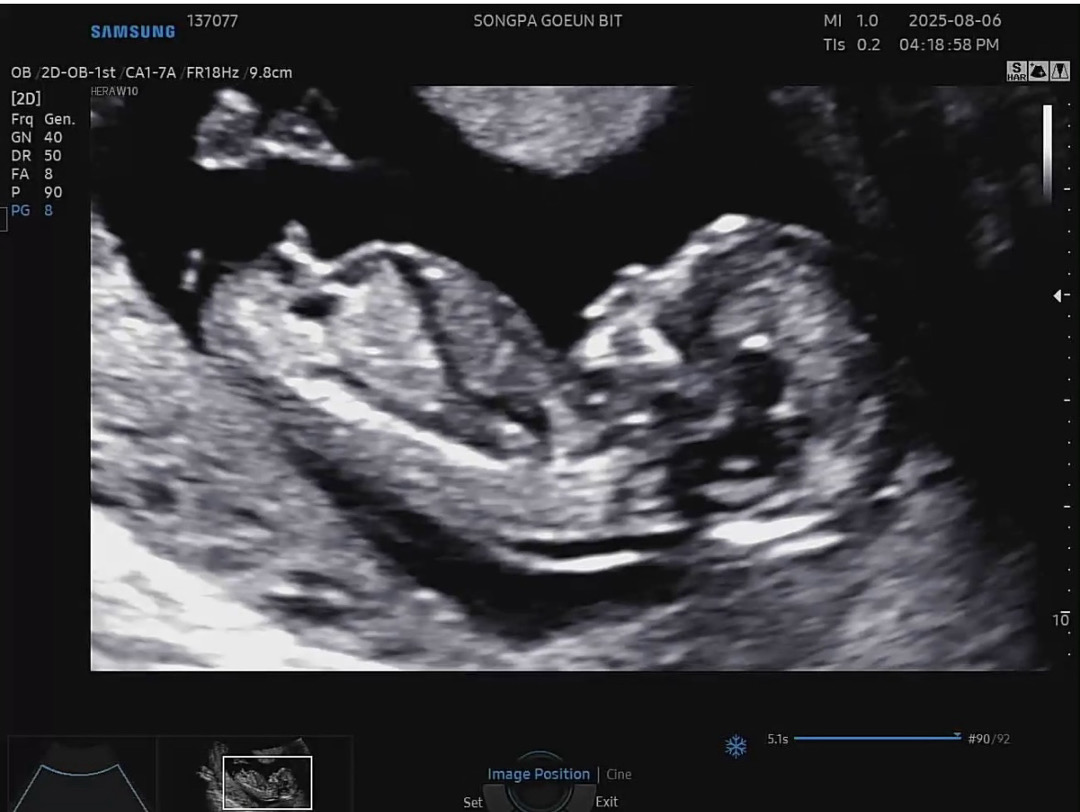

12주 6일 각도법 봐주세요😍

아들같기도 딸같기도 하네용 봐주시면 감사하겠습니다 ㅎㅎ

아들 각도에용~!

아들같아용!

딸!

딸이에요